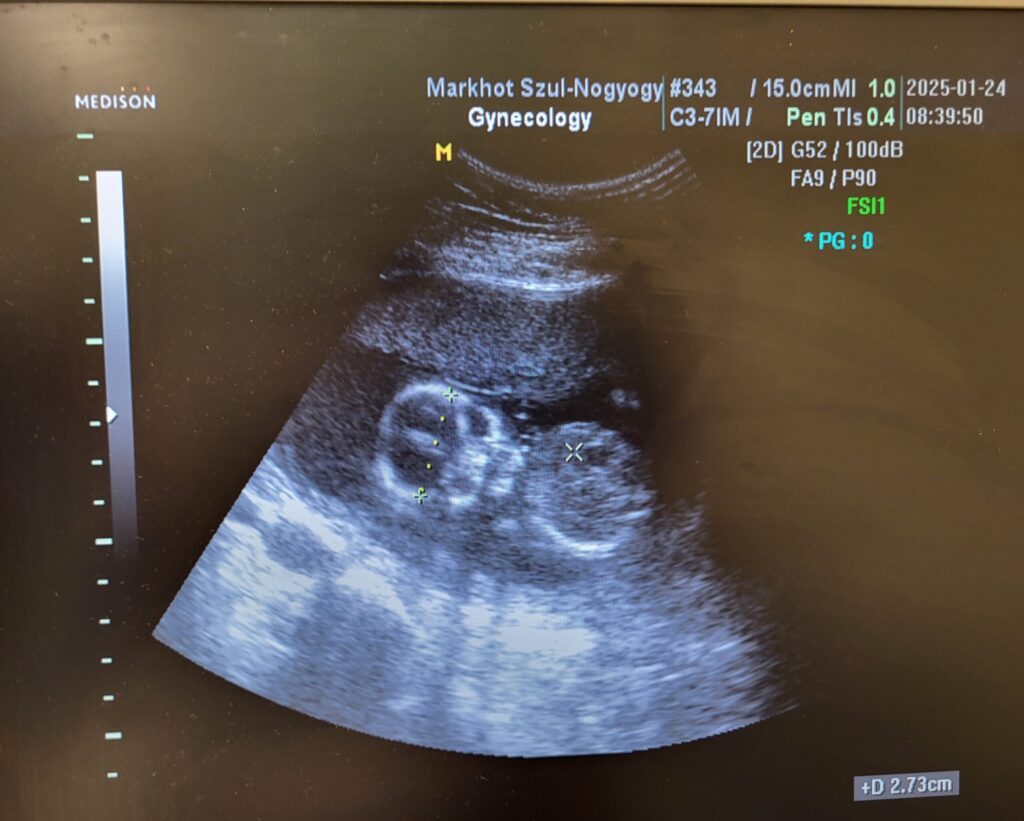

Én a nem túl rózsás egészségi állapotomra való tekintettel nőgyógyászhoz is elmentem egy kolléganő/ barátnő kíséretében. Mikor sorra kerültem, a manuális vizsgálatnál még semmi rendhagyó nem történt. Néztem a plafont és vártam, hogy vége legyen. Aztán előkerült az ultrahang. Ebben sem volt semmi meglepő, mert a korai klimax miatt a méhem sorvadni kezdett. Tudtam, hogy az orvos csak alapos.

Aztán elkezdte sorolni: ”igen…, itt a kis feje…” -erre még nem figyeltem fel. Méhnyak ugyan van és méhfejről még nem hallottam, pláne becézve, de néha én is összehordok hetet-havat. Akkor neki is szabad. De folytatta: ”…a kis mellkasa, karok, kezecskék…” Bevallom, ez már gyanús volt. Odafordultam és a szám is tátva maradt: a babám pont felém fordult, mintha csak azt akarta volna, hogy minden kétséget kizáróan felismerjem, mit is látok.

Roppant értelmesen, egészségügyi dolgozóhoz méltón rá is kérdeztem. Azt hittem ugyanis, hogy valakinek videót csináltak és véletlen az indult el. (Tudom, igazi informatikai zseni vagyok…) Ezt is megkérdeztem. A következő pár perc azzal telt, hogy az orvos bizonygatta, hogy a kisbabám látjuk, én meg, hogy az lehetetlen, mert meddő vagyok. Végül a doki unta meg hamarabb és megmozgatta az ultrahangot a hasamon: ”nézze, itt van, mozog!” Sírva fakadtam.

Az orvos tanácstalan volt. Szerintem akkor hitte el, hogy fogalmam sem volt róla, hogy babát várok. (Ami rettentő ciki, mert 16 hetes és 4 napos volt a kis Ebihal…) Bizonytalan hangon megkérdezte: ”…akkor most örülünk..?” Alig tudtam elhüppögni, hogy igen! Nagyon! Teljesen sokkolt a dolog. Uramatyám, én végig dolgoztam! Energiaitalt is ittam! Csak egészséges legyen! Mit mondjak a kedvesemnek? Hogy mondjam el? Mostmileszmostmileszmostmilesz??? Úgy összezavarodtam, a fenti kép is csak azért készülhetett el, mert az asszisztensnő megkérdezte, hogy akarom-e lefotózni a monitort. Hogyne akartam volna!